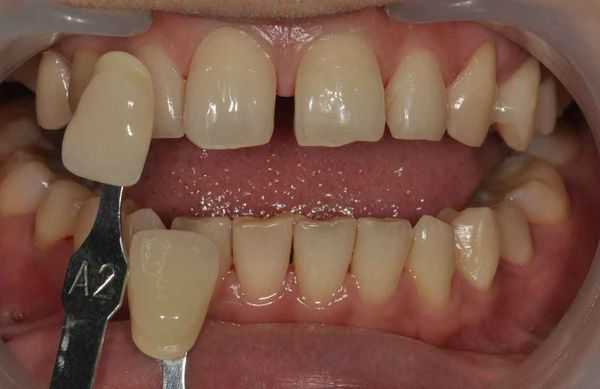

- Виниры или композитный бондинг. Подразумевают накладывание на зубы накладок (виниров) или слоя композитного материала. Композитным называют материал, состоящий из двух или более компонентов с разными химическими свойствами. В сочетании эти компоненты затвердевают и образуют зубчатое вещество. Виниры и композитный бонд лучше всего использовать для закрытия одного или двух промежутков. Фарфоровые виниры помогают заполнить небольшие диастемы. В этом случае стоматолог делает винир больше, чем зуб, и излишки материала заполняют пространство. Обычно лечение винирами требует двух посещений: при первом приёме стоматолог подготовит всё для изготовления виниров, при втором — установит их на зубы.

Прямая реставрация. Используется при микродентии, при неправильной форме коронок. Стоматолог выполняет эстетическую реставрацию, «наращивая» коронки так, чтобы закрыть промежуток. Способ используется при правильном расположении зубных корней (появление щербинки связано только с формой и размером центральных резцов).

Установка виниров. Виниры маскируют эстетический недостаток, закрывают диастему. Применяют при микродентии, при незначительных дефектах в строении зубного ряда (затрагивают только центральные резцы). Виниры устанавливаются на передние зубы так, чтобы выровнять их, убрать промежуток, восстановить эстетику улыбки.